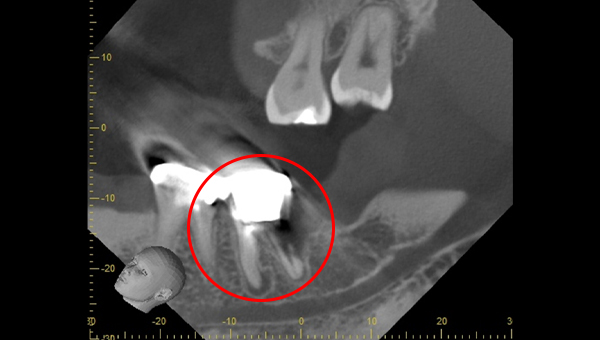

CT像①

CT像②

説明:

CT像です。根の中央を超えて虫歯が広がっているのがわかります。そこに上の親知らずを移植することに

しました。

CT画像

骨の状態はそこまで悪くないが、欠損が大きい。